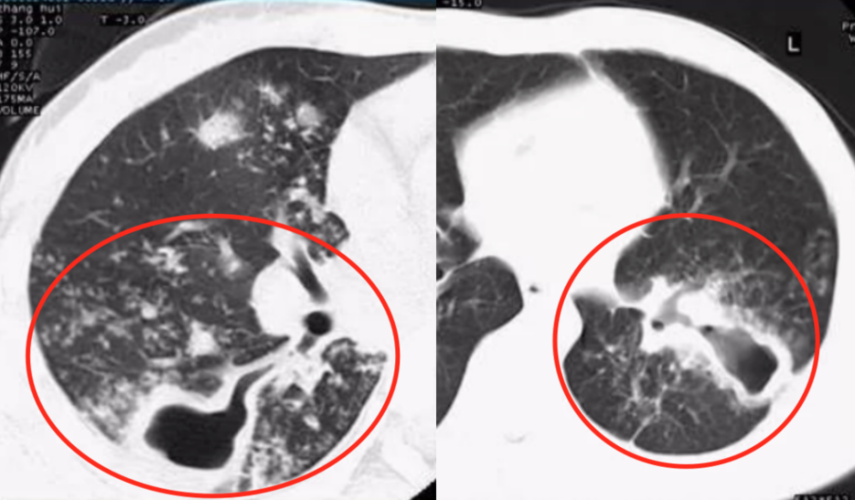

上图所示,这是一个典型的肺结核的空洞(左图),可见不规则空洞与支

图10 粟粒性结核.65岁女性,患有肺炎,虽然治疗但未改善.

空洞型肺结核